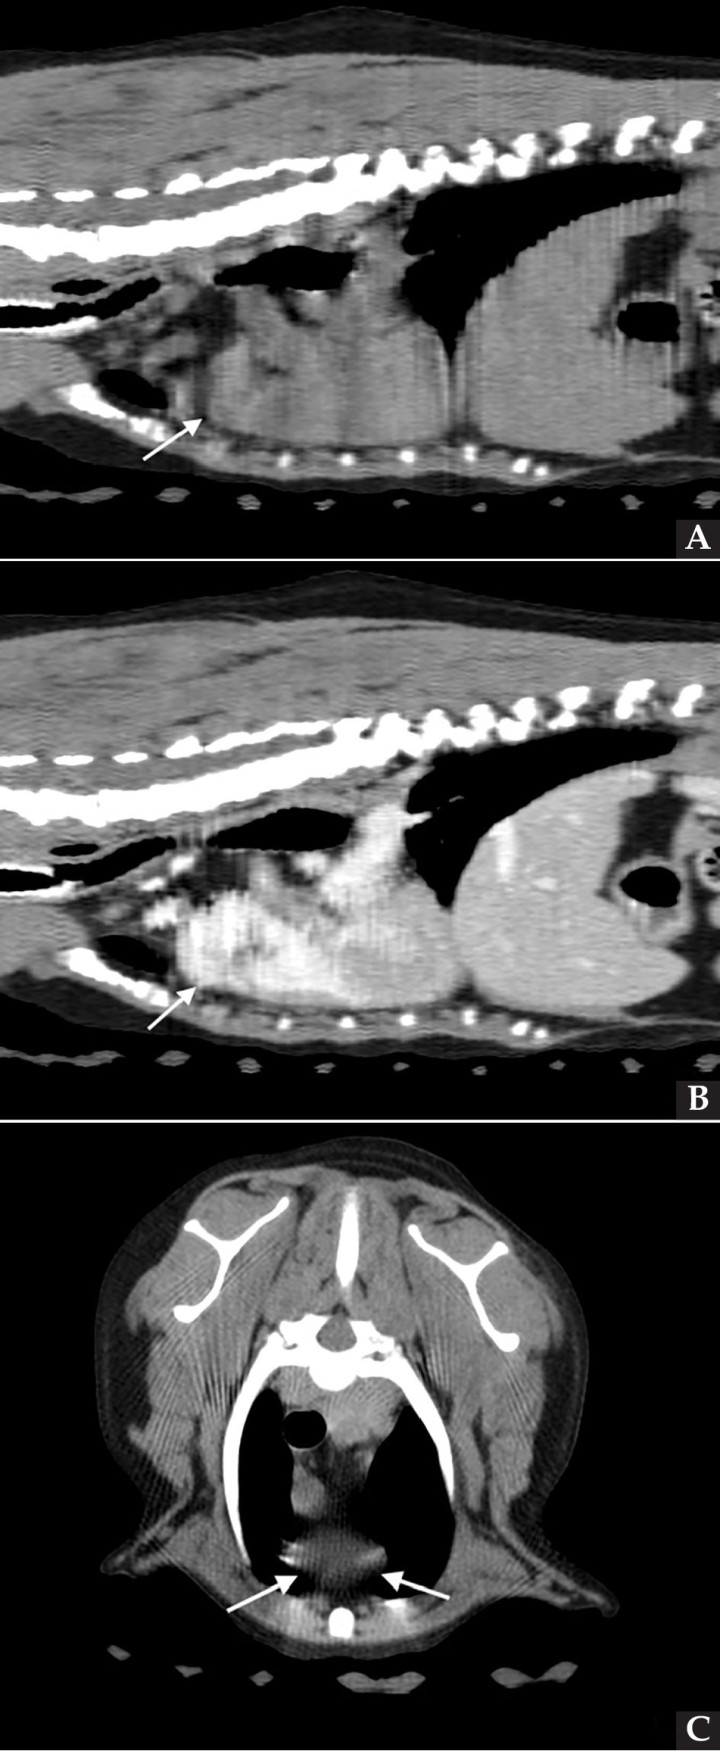

Se realizaron radiografías torácicas y en la proyección lateral derecha se observó, craneal a la silueta cardiaca, una opacidad tejido blando mal definida que producía efecto silueta positivo con esta. La tráquea se visualizó desplazada dorsalmente y el atrio izquierdo aumentado de tamaño. El parénquima pulmonar mostraba un aumento de opacidad en su área caudodorsal, compatible con un patrón pulmonar intersticial no estructurado difuso, el cual se consideró normal debido a que la radiografía fue tomada en fase espiratoria inicial y a la condición corporal del paciente. En la proyección ventrodorsal, el mediastino craneal se observó en el límite superior de tamaño, presentándose un tamaño dos veces superior a la anchura de la vértebra torácica (Fig. 1). Este cambio es compatible con una imagen artefactual secundaria a la leve rotación que presenta la radiografía y a la condición corporal del paciente. El diagnóstico radiológico más probable fue una masa mediastínica craneoventral y cardiomegalia izquierda. En la ecocardiografía transtorácica se confirmó el diagnóstico de enfermedad degenerativa de la válvula mitral (EDVM), presentando engrosamiento, prolapso e insuficiencia valvular, dilatación del atrio izquierdo (AI/AO=1,9) y leve aumento de las dimensiones diastólicas del ventrículo izquierdo normalizado al peso del paciente (NLVDD=1,7). Las presiones de llenado intracardiacas se estimaron como normales, ya que el flujo transmitral presentó un patrón de relajación anómala y la velocidad pico de E fue de 0,8 m/s. En función de estos hallazgos se confirmó el diagnóstico de enfermedad degenerativa valvular mitral con cardiomegalia izquierda y sin hallazgos compatibles con insuficiencia cardiaca congestiva, por lo tanto en estadio ACVIM B2. En las vistas ecocardiográficas paraesternal derecha de 4 cámaras y apical izquierda de 4 cámaras se visualizó una estructura redondeada y anecógena de 15 mm, con flujo sanguíneo en Doppler color, adyacente al corazón (Fig. 2). Este hallazgo es compatible con dilatación aneurismática de las estructuras vasculares o las cavidades cardiacas, si bien no se pudo establecer continuidad con ninguna de ellas en la ecografía. La valoración con Doppler pulsado de los tractos de salida del ventrículo izquierdo y derecho mostró la repetición de un perfil de flujo con disminución del área bajo la curva en el segundo latido con respecto al precedente.

<p>Radiografías torácicas en proyección lateral derecha (<strong>A</strong>) y ventrodorsal (<strong>B</strong>) donde se visualiza el área de opacidad de tejido blando craneal a la silueta cardíaca (flechas blancas). En la proyección ventrodorsal se visualiza el mediastino craneal que se presenta en el límite superior de grosor (flechas rojas).</p>

Figura 1

Radiografías torácicas en proyección lateral derecha (A) y ventrodorsal (B) donde se visualiza el área de opacidad de tejido blando craneal a la silueta cardíaca (flechas blancas). En la proyección ventrodorsal se visualiza el mediastino craneal que se presenta en el límite superior de grosor (flechas rojas).